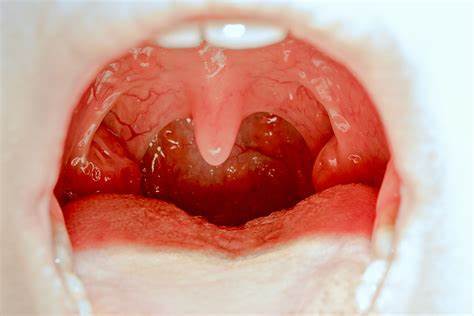

扁桃體一邊腫大但不痛,可能與單純性扁桃體腫大等生理性原因有關(guān),也可能與病理性原因有關(guān),如慢性扁桃體炎、扁桃體淋巴瘤、咽旁間隙腫瘤。建議及時(shí)前往醫(yī)院的耳鼻喉科就診,可以進(jìn)行血常規(guī)、喉鏡等相關(guān)檢查,有助于判斷病情,從而進(jìn)行針對性治療。一、生理性原因:可能是單純性扁桃體一邊腫大,扁桃體為淋巴組織,通常會參與機(jī)體的免疫反應(yīng),兒童時(shí)期接觸外界刺激的機(jī)會逐漸增多,免疫功能較活躍,扁桃體可能會顯著增大,此時(shí)多為生理性肥大,且一般沒有明顯不適感,查體扁桃體無紅腫、表面光滑,建議觀察,定期復(fù)查,隨訪即可。

口臭既然是咳出來的“小米?!?!

隨著咳嗽、或者打噴嚏等動作,吐出或咳出像小米粒的黃白色塊狀物體,捏扁了聞起來臭臭的。而有的人因?yàn)檠屎聿贿m來就診,檢查過程中可以看到有黃白色不規(guī)則物體嵌頓于扁桃,稱為“扁桃體結(jié)石”。扁桃體結(jié)石是扁桃體內(nèi)形成的結(jié)石樣物質(zhì)。我們常說的“扁桃體”通常就是張口能看到的位于懸雍垂兩側(cè)的那兩團(tuán)組織。其實(shí)扁桃體表面并不光滑,相反,扁桃體上皮在有限的空間內(nèi)選擇了折疊,并陷入扁桃體實(shí)質(zhì)內(nèi),形成深淺不一的“扁桃體隱窩”。每個(gè)成人的腭扁桃體平均有10-20個(gè)隱窩,但是這也給扁桃體結(jié)石形成創(chuàng)造了“藏污納垢”的條件:長期的炎癥和隱窩內(nèi)落入的食物殘?jiān)⒓?xì)菌、代謝產(chǎn)物形成的團(tuán)塊和膿性分泌物、脫落細(xì)胞以及腺體分泌的鈣鹽,會不斷包裹、沉積,形成類似結(jié)石樣的干酪物,逐漸增大并向排出。小的扁桃體結(jié)石并不會引發(fā)癥狀,而隨著扁桃體結(jié)石的增大與向隱窩外的排出,可能引發(fā)以下癥狀:咽部異物感疼痛(扁桃體結(jié)石直接刺激)耳痛(舌咽神經(jīng)放射性疼痛)吞咽困難(咽腔運(yùn)動牽拉)口臭因扁桃體結(jié)石中通常存在細(xì)菌及其產(chǎn)物,可具有特殊臭味,這也是部分人群即使非常注意口腔衛(wèi)生的情況下仍存在口臭的原因。扁桃體結(jié)石的治療扁桃體結(jié)石位于扁桃體隱窩中,因此最為直接有效的處理手段即為人工清理??梢圆扇“〝D壓、抓取、沖洗等措施(如無明顯外移跡象則不建議強(qiáng)行清理),如扁桃體結(jié)石能順利排出則可有效緩解癥狀。除此之外,加強(qiáng)口腔衛(wèi)生如飯后漱口認(rèn)真刷牙可能有助于減少扁桃體結(jié)石的發(fā)生。醫(yī)學(xué)處理手段正因結(jié)石是發(fā)自扁桃體隱窩,于是有一些采用激光燒灼、熱力學(xué)破壞(等離子)等方法開放扁桃體隱窩、以期減少扁桃體結(jié)石生成的報(bào)道。此外,雖然扁桃體隱窩結(jié)石是口臭的一個(gè)病因,但對于能夠排除諸如口腔衛(wèi)生、牙健康等其它可能病因并經(jīng)自行清潔扁桃體隱窩等手段充分處理后仍存在明顯持續(xù)的口臭者,還可考慮行扁桃體部分或者完整切除手術(shù)。